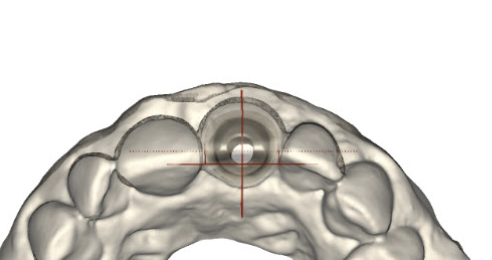

(20.)  Molar custom abutment.

Figure 20

(21.)  Molar custom abutment.

Figure 21

(22.)  Molar custom abutment.

Figure 22

(23.)  Molar custom abutment.

Figure 23

(24.)  Molar custom abutment.

Figure 24

(25.)  Molar custom abutment.

Figure 25

(26.) Premolar custom abutment.

Figure 26

(27.) Premolar custom abutment.

Figure 27

(2828.) Premolar custom abutment.

Figure 28